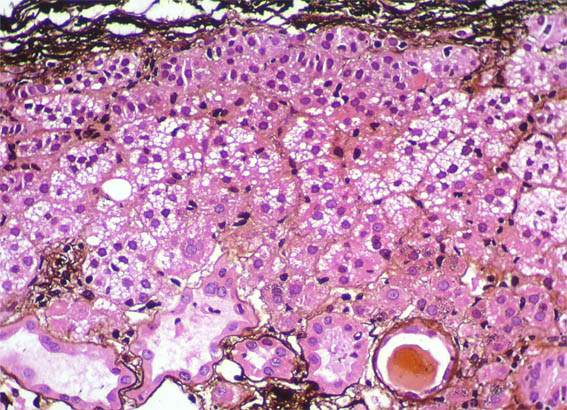

Figura 8. Plata-metenamina, X100.

Figura 9. Plata-metenamina, X200.